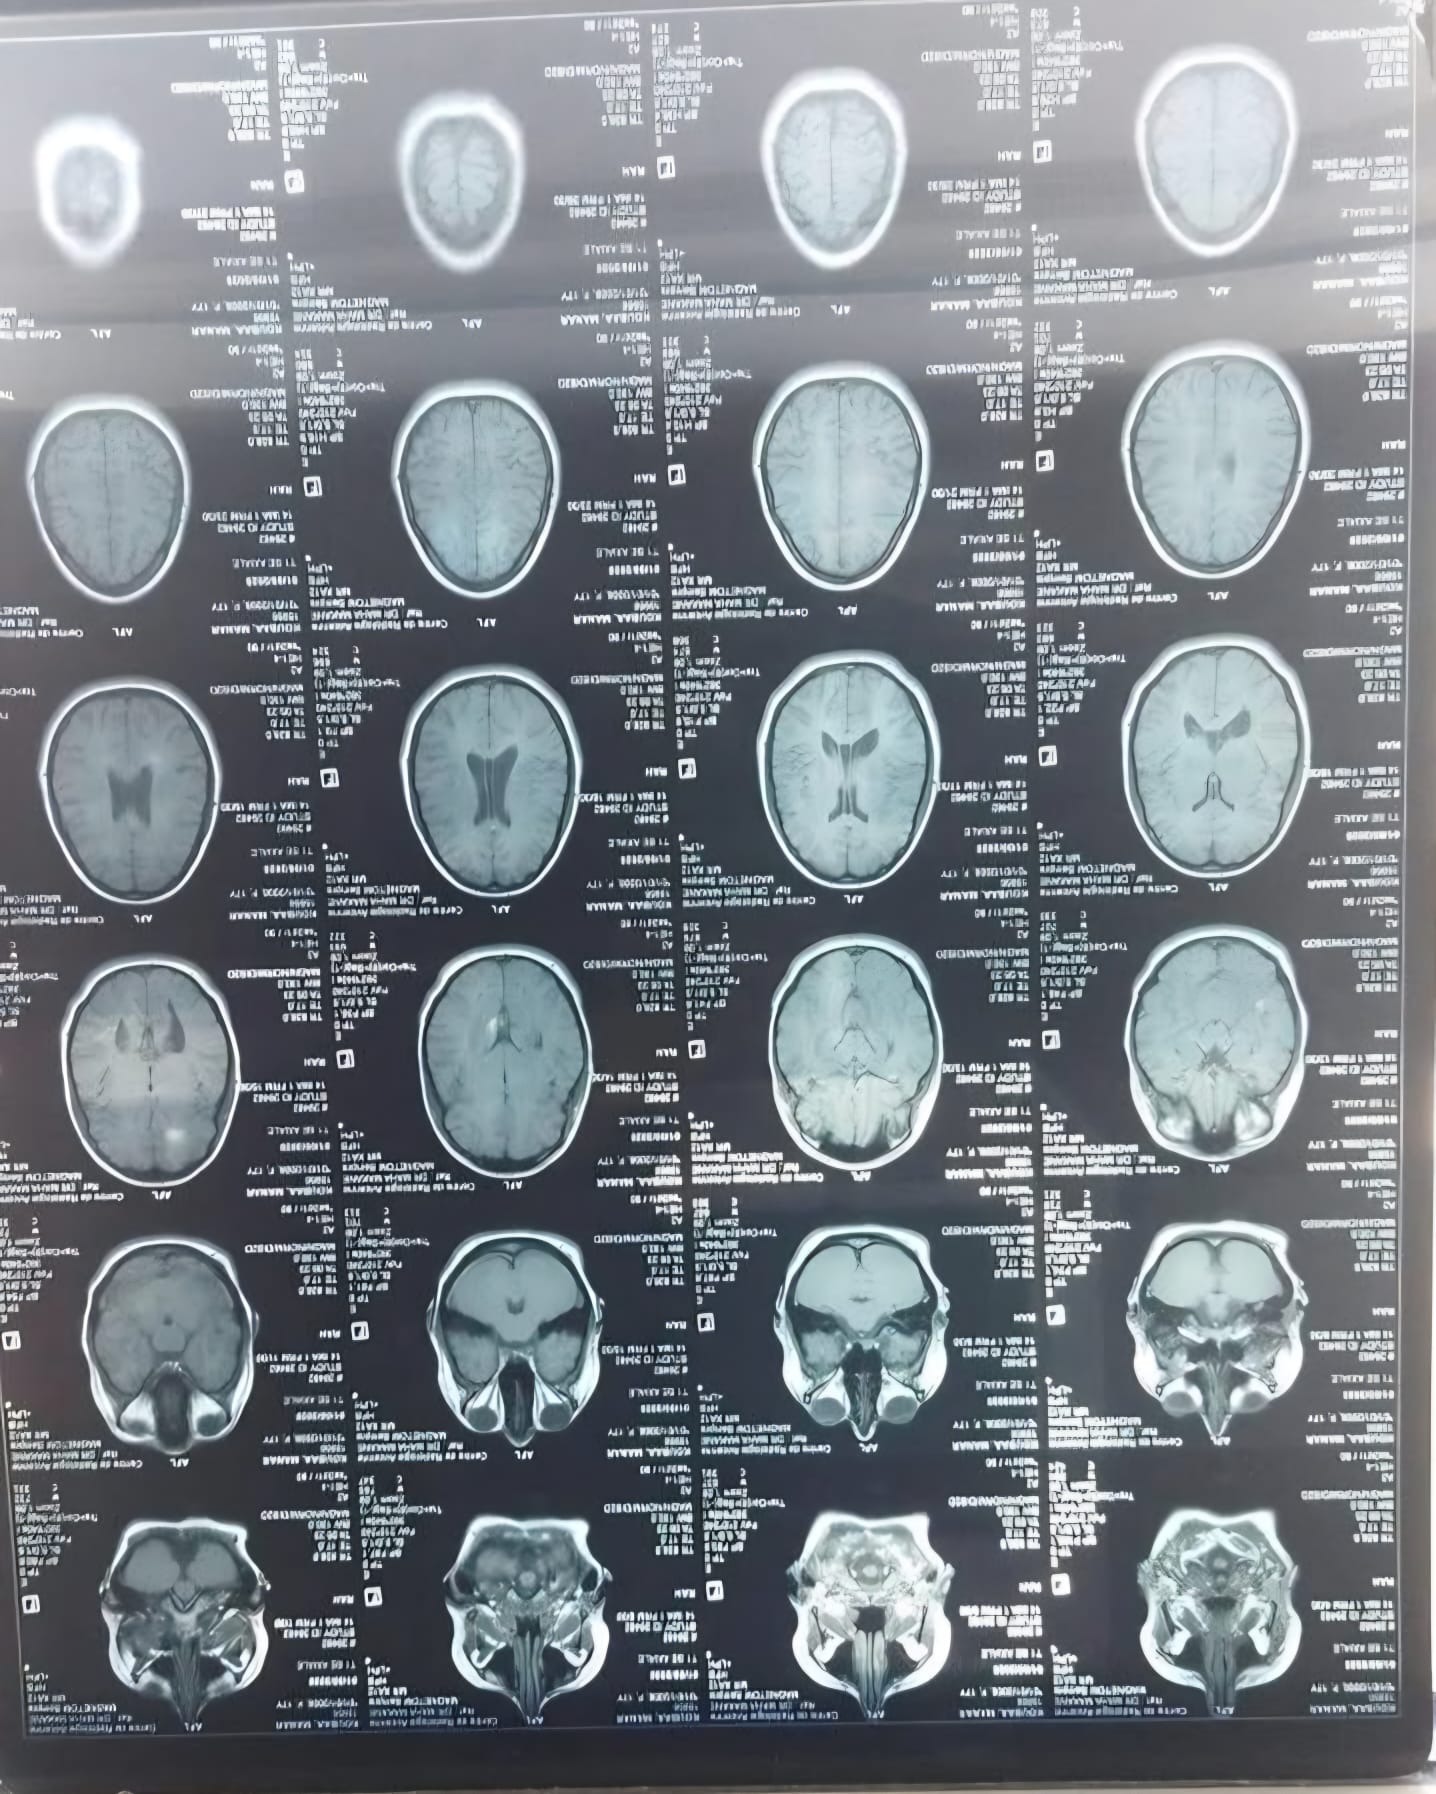

Ik ben Manar, ik ben 17 jaar oud. In mei 2025 heb ik de diagnose MS gekregen. Ik had veel last van duizeligheid, vermoeidheid en uiteindelijk dubbelzien. Uit verschillende onderzoeken is de diagnose MS vastgesteld. Iedere maand krijg ik via een infuus in het ziekenhuis medicatie toegediend, dit zorgt ervoor dat de ziekte geremd wordt. Helaas merk ik toch nog veel lichamelijke klachten waar ik dagelijks mee te maken heb. Dit beinvloed mijn dagelijks leven en het voortzetten van mijn studie. Al hamdoulilah 3la kouli hal.

Om te voorkomen dat mijn lichamelijke gezondheid niet verder achteruit gaat wil ik een stamcelbehandeling ondergaan in het buitenland. Een HSCT-behandeling, een intensieve behandeling waarbij het immuunsysteem wordt gereset. Deze behandeling kan de ziekte niet genezen, maar wel stopzetten en verdere verergering voorkomen. Deze behandeling kost € 65.000. Ik vertrouw er op met behulp van Allah en onze geweldige ummah dit bedrag te kunnen verzamelen, in sha allah.